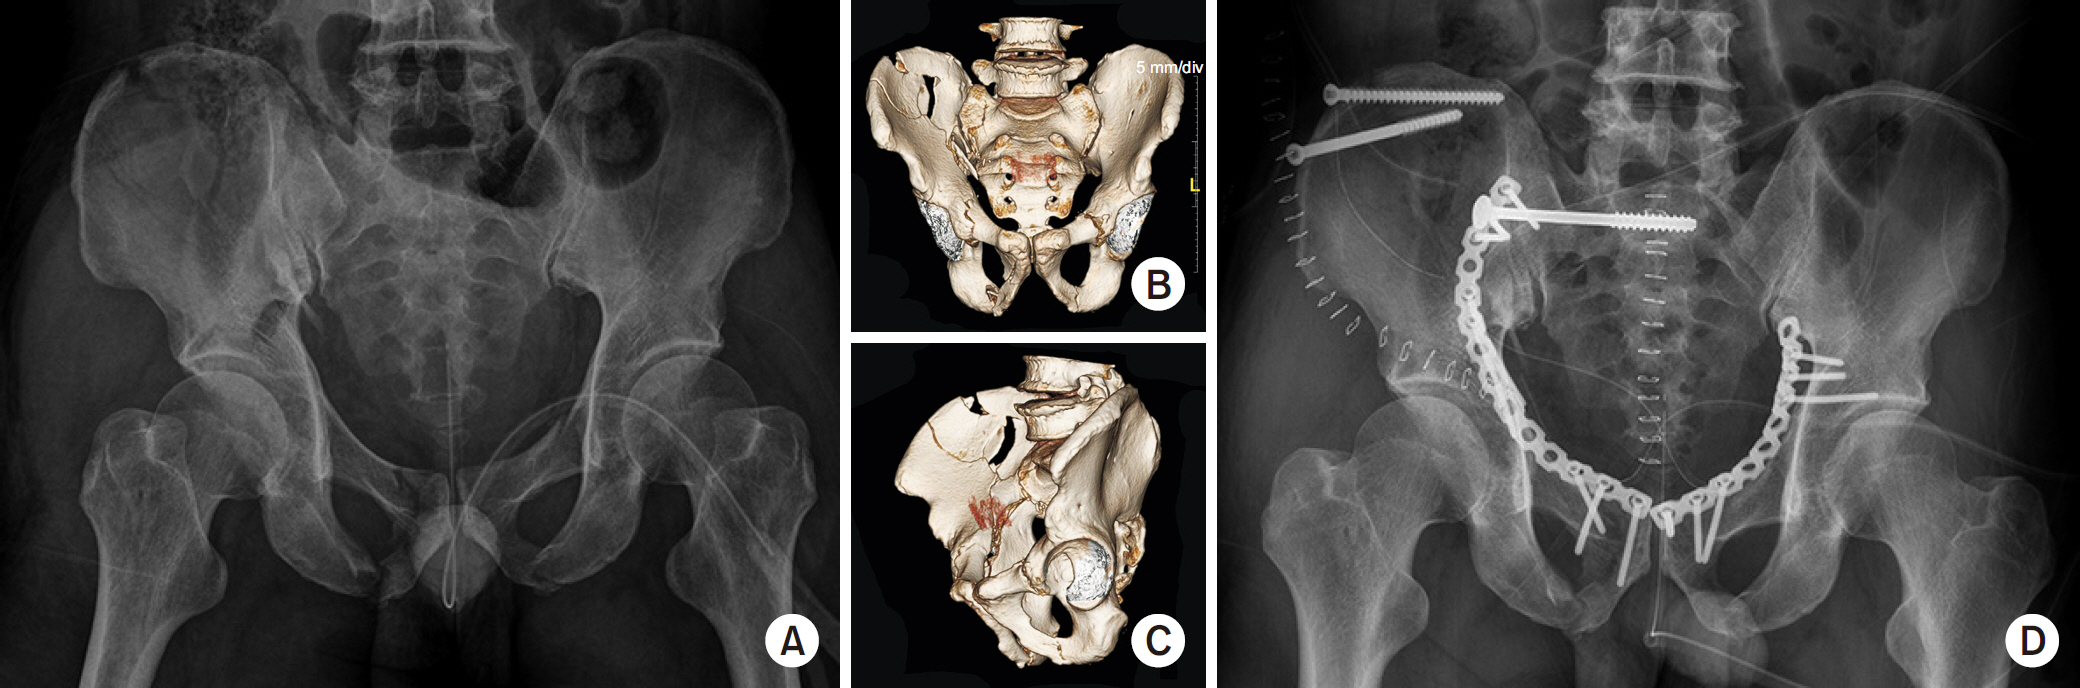

Fig. 3.

Modified Stoppa approach for a bilateral pelvis ring injury and right acetabular fracture. (A) Initial pelvis X-ray showing the right acetabular anterior column fracture with the right sacral alar fracture and left pubic fracture. (B, C) Three-dimensional reconstruction images. (D) Postoperative pelvis anteroposterior.